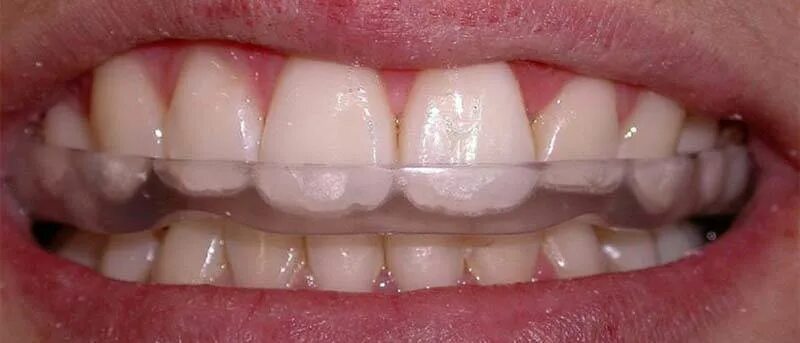

Зубы зажаты